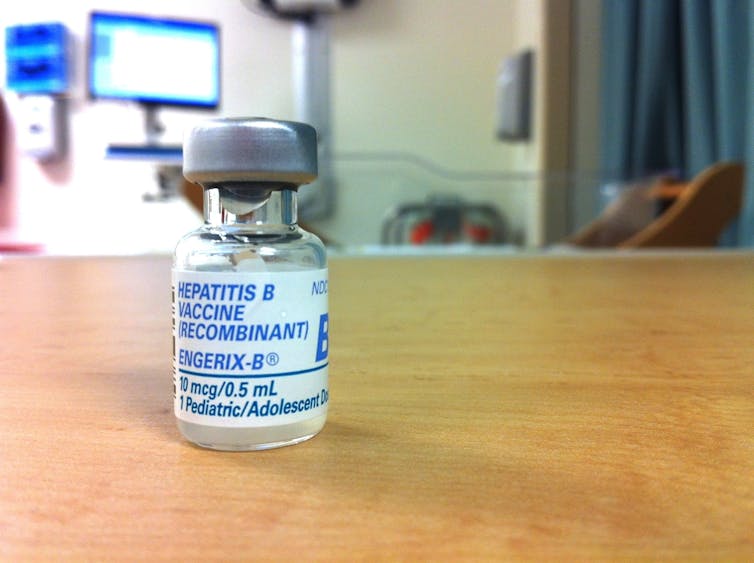

Hepatitis B virus and liver cancer

In another type of epidemiological study, called a cohort study, a large number of healthy people are enrolled, blood samples are taken and they are asked questions about personal habits and exposures. They are then followed for many years to see who gets cancer.

For example, the primary causes of liver cancer were not understood until epidemiologist R. Palmer Beasley began a large cohort study in Taiwan in 1975. He enrolled 22,707 otherwise healthy men and followed them for several years. Of the sample, 3,454 were chronically infected with hepatitis B virus (HBV). After several years of follow-up, there were 40 new cases of liver cancer in the HBV carrier men and only one in the much larger noncarrier group.

The cohort study clearly showed that HBV can cause liver cancer. And in this case, understanding the biology of HBV and how it is transmitted has led to prevention of liver cancer by making a vaccine against the virus.

This knowledge has also greatly improved treatment because now chronic HBV carriers are tested annually for alfa fetoprotein in the blood to screen for the presence of cancer. As a result, liver cancer is caught much earlier than in the past.